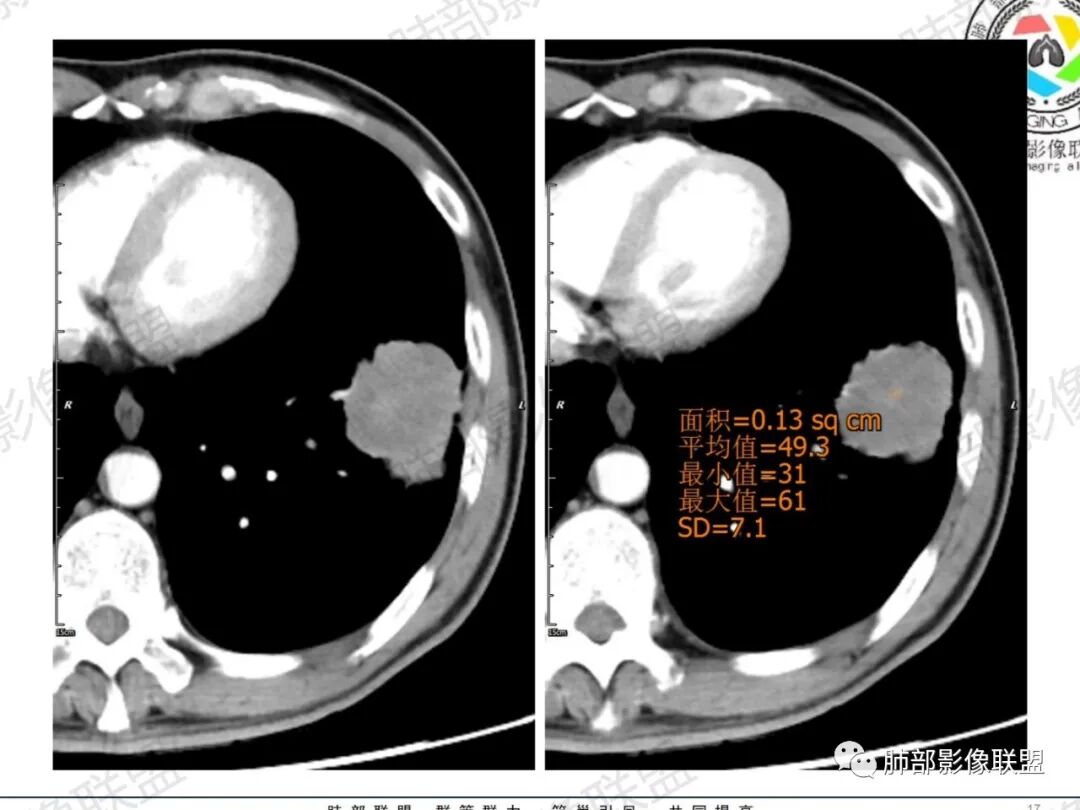

LCNEC最常见的影像特征包括:(1)肿块发生部位:周围型肺癌为主,少数发生于肺中央。(2)肿块大小及形态。因肿瘤细胞生长迅速常形成较大肿块,因此其体积一般较大,直径常在3~10cm范围内,病灶常为不规则形软组织肿块。(3)肿块边界。多数学者报道大多数肿块边界清晰,边缘呈分叶状,毛刺征及“胸膜凹陷征”少见,认为与该病对周围组织浸润较轻及较少产生纤维瘢痕组织牵拉有关联。(4)肿块密度、强化特点及代谢情况。据文献报道,该类肿瘤因体积较大CT上常见软组织肿块,且多数密度不均匀,内见囊变坏死区,增强后呈轻或中度不均匀强化(可见强化者占75.7%),认为其强化特点与其内部肉眼可见坏死灶和肿瘤较大直径有关。(5)伴随症状及远处转移。该病恶性程度高,侵袭性强,常侵犯邻近结构,如胸膜、心包、邻近骨质或纵隔内组织等,易出现纵隔淋巴结转移,部分发生肺内及远处转移,少数早期可出现广泛远处转移。

LCNEC患者空洞、钙化、阻塞性肺炎、肺不张、积液这些CT特征较少见,少见支气管充气征。